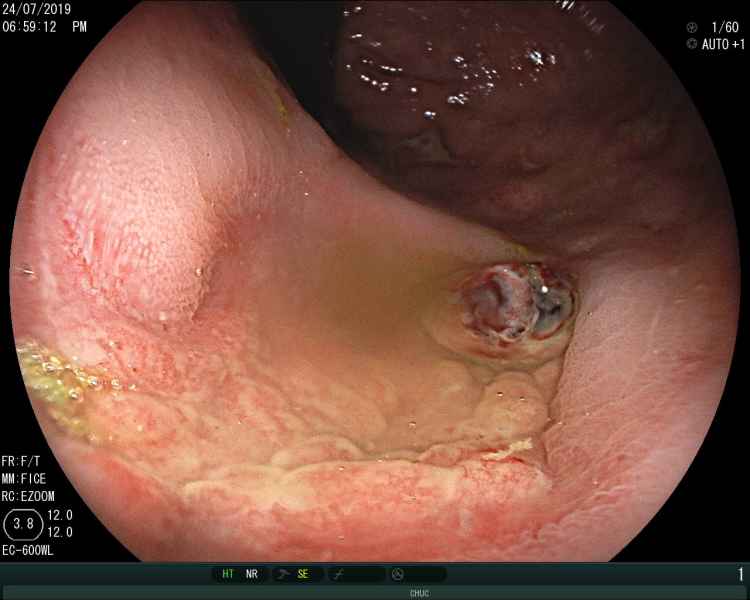

A messy web - 1.º Prémio (Fotografia)